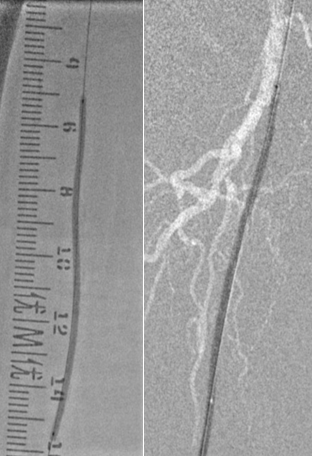

中等长度 、轻微钙化的股浅动脉病变

股浅动脉中等长度病变(10-20cm)合并轻微钙化,因病变范围适中、钙化程度较轻,需兼顾 “微创开通” 与 “长期通畅”。巧克力球囊凭借均匀扩张、低血管损伤的核心优势,成为这类病变的理想选择,可高效完成血管准备,适配 “无支架” 治疗理念。

★ 巧克力球囊

Chocolate 5-120mm

除近端残余狭窄外,效果良好